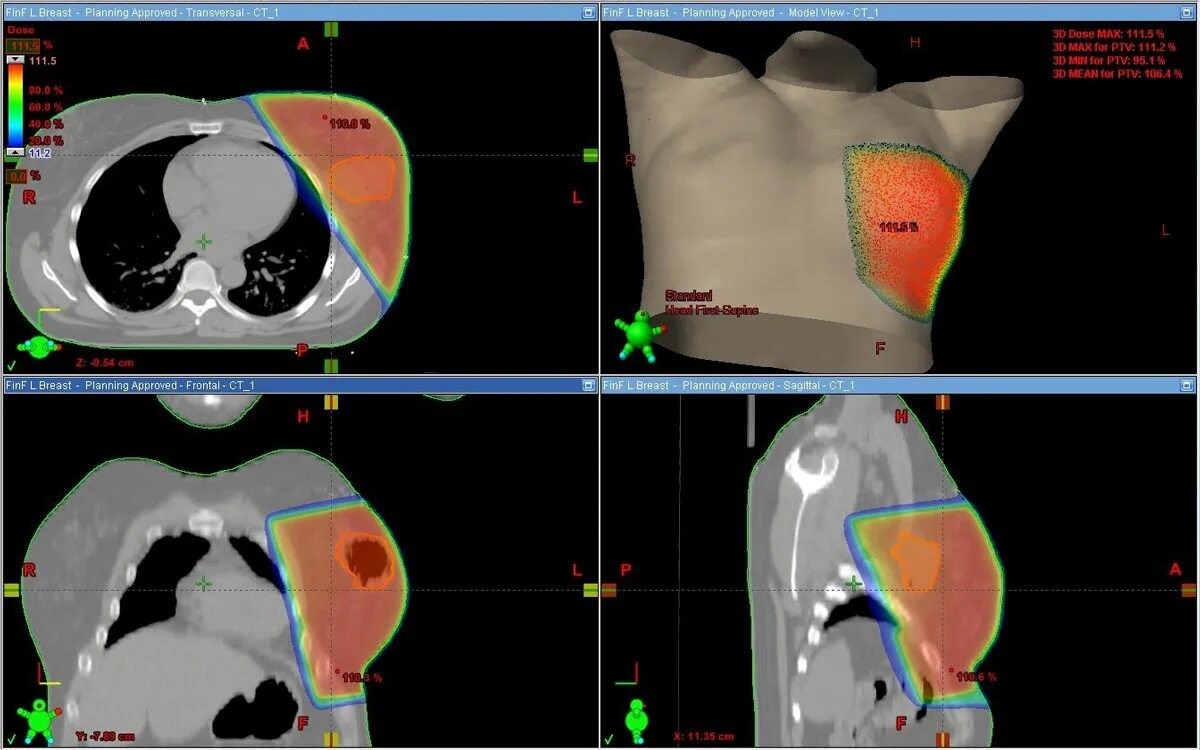

Делают ли кт молочных желез